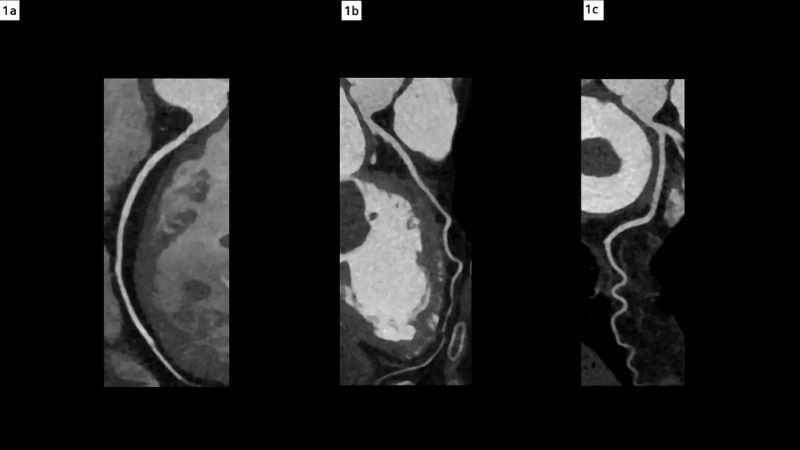

Cardiac myxoma (heart tumor) is a rare benign tumor usually found in the left atrium of the heart. Visual examples show its mass obstructing blood flow and altering cardiac function.